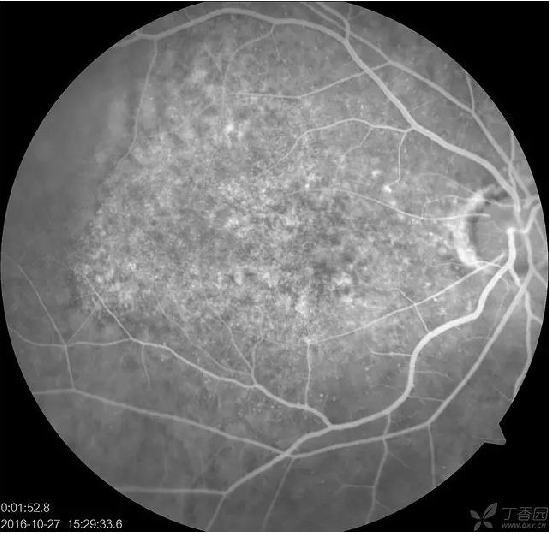

患者,女,48岁,突发左眼视力下降3天,素健,查体:VOD 0.6 VOS HM 出血下方可见橘黄色病灶。考虑PCV,因为出血太大,没敢看,让她去省里了。后面就失访了。请教这个病人pcv是否正确?该如何处理,止血还是活血?OCT上是指样征么?